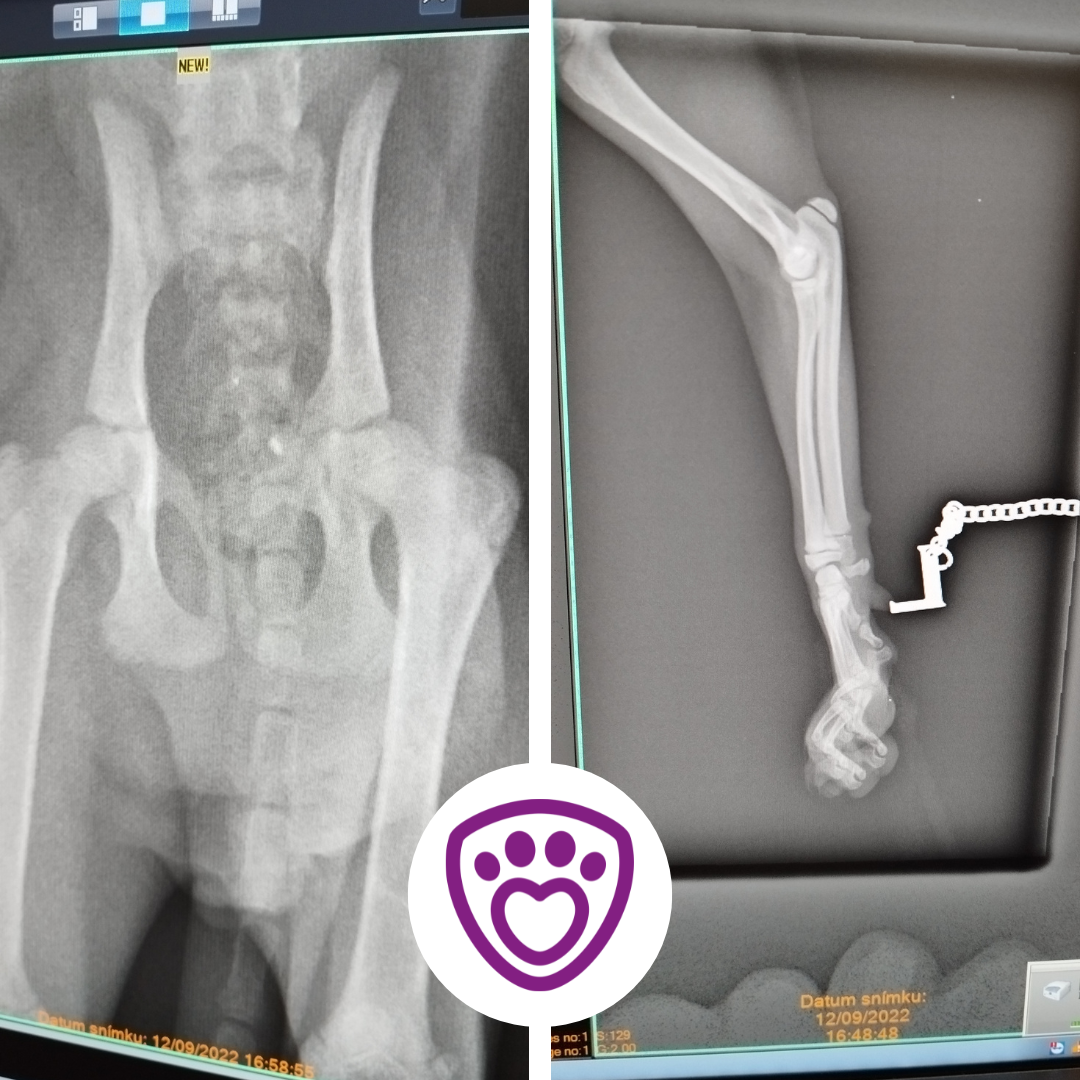

He was found injured, probably hit by a car. He was without help for several days with a complicated fracture of his front leg and pelvis. Small kitten that no one wanted.

At first, we thought only his front leg was not allright. He has a complicated joint fracture there. Unfortunately, that wasn't all, the vet found out his pelvis is fractured as well. 😨

Wormy is to undergo a demanding surgery, during which they will try to save his front leg. The area around the pelvis has to be open, cleaned and sew up to suppress the possible infection.